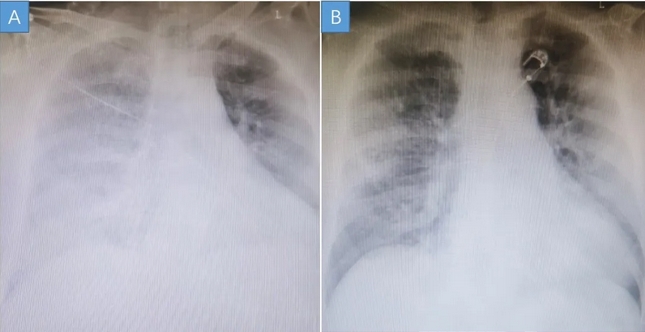

患者入院后床旁胸片(A)和治疗后好转的胸片(B)对比